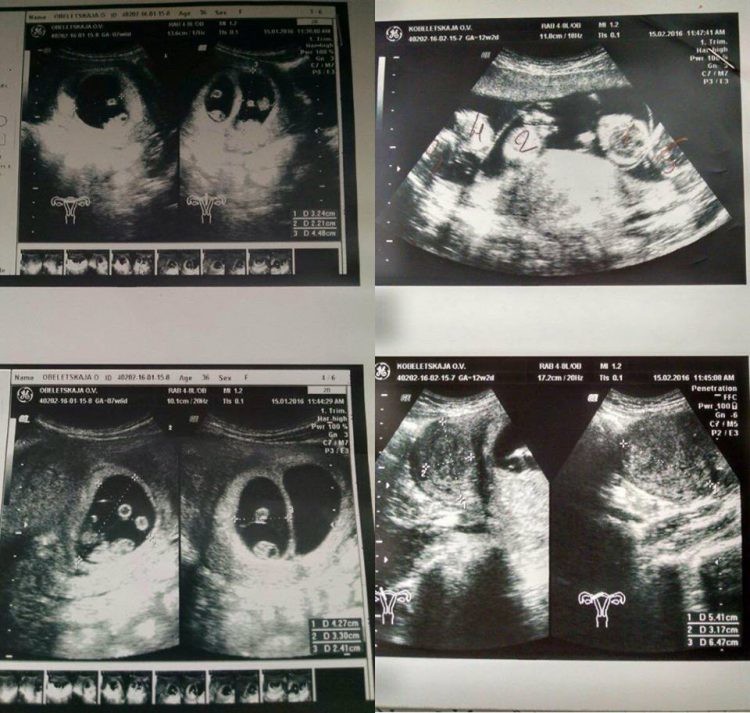

Итак, по итогу по результатам УЗИ выяснилось, что Оксана ждет пятерняшек! Такой редкий случай, когда без искусственного оплодотворения происходит такое чудо! Статистика говорит о случайности такого явления 1 к 55 миллионам! Пока Оксана переваривала эту новость, по больнице быстро пронеслась молва об уникальной пациентке, такого в их практике не было, и, думаем, не будет за всю их жизнь!

«Все было как у всех: голый живот, гель и датчик. Но когда доктор начала смотреть в экран, у нее сильно изменилось лицо, и я не на шутку испугалась,» — вспоминает Оксана. — «Помню как она начала вслух считать количество плодов и приговаривала, что за такое мне должны подарить дом у моря…